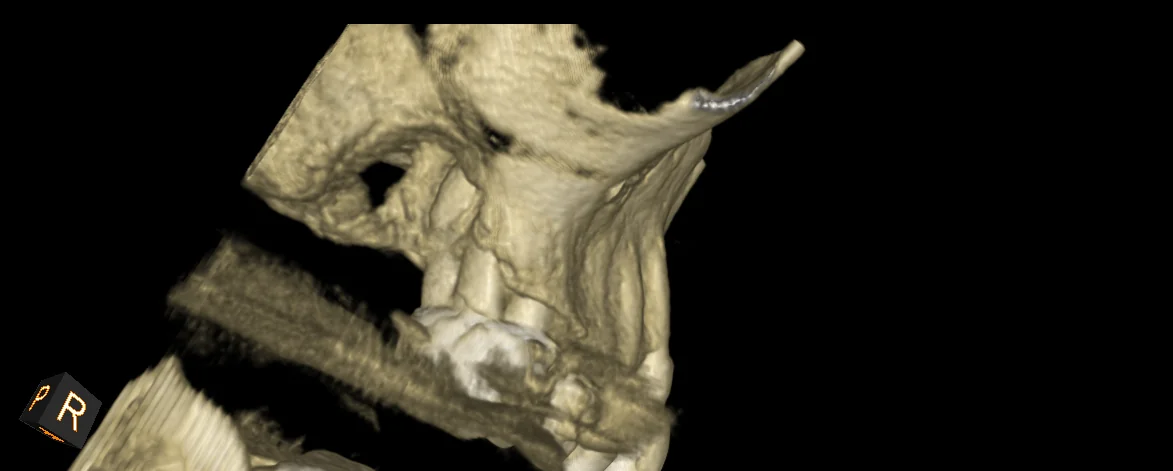

What the CBCT Showed

The 3D imaging revealed several findings that didn't fit a routine endo-perio presentation: calcification within the canal, furcation involvement, and — most concerning — irregular bone borders with cortical plate erosion. The borders weren't smooth the way you'd expect with a standard infection or cyst. They were ragged and ill-defined, which in rare cases can indicate malignancy.

Our working differential included a combined endo-perio lesion, a vertical root fracture, and — given the irregular CBCT borders — possible maxillary sinus carcinoma. Sinus malignancies account for less than 0.2% of maxillary sinus pathologies, but the cortical plate erosion pattern on this CBCT was not something we could ignore.

• Irregular CBCT Borders Are a Red Flag: Smooth, well-defined radiolucencies suggest infection or cysts. Ragged, ill-defined borders with cortical plate erosion should raise suspicion for malignancy and warrant further investigation.